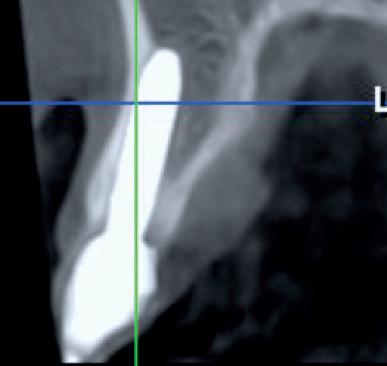

• Apprentissage et maîtrise de la lecture du scanner : planifications virtuelles.

• Anticiper la position clinique de l’implant à partir de sa position virtuelle.

L’objectif pédagogique réside également dans la volonté qu’aucun praticien ne se retrouve seul face à des patients présentant des plans de traitements simples ou complexes, seul aussi devant des interprétations

de scanners classiques ou délicates, ou seul encore pour effectuer des chirurgies courantes ou relevant de techniques avancées et ceci pendant et après le cursus.